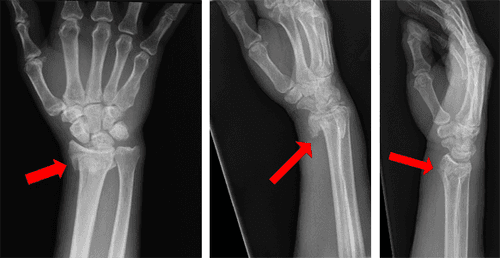

डॉक्टर बहुधा फ्रॅक्चर आहे की नाही हे जखमेची तपासणी करून आणि एक्स-रेच्या मदतीने सांगतात. पण कधीकधी एक्स-रेमध्ये फ्रॅक्चर असल्याचे दिसत नाही. यात मुख्यतः काही प्रकारचे मनगटाचे फ्रॅक्चर, खुब्याचे फ्रॅक्चर, आणि स्ट्रेस फ्रॅक्चर्स यांचा समावेश होतो. अशावेळी फ्रॅक्चरचे निदान करण्यासाठी डॉक्टर सिटी स्कॅन, एमआरआय किंवा बोन स्कॅन या तपासण्या करायला सांगतात.

कधीकधी मनगटाचे हाड फ्रॅक्चर होते, त्यावेळी सुरुवातीला एक्स-रे नॉर्मल दिसतो. अशावेळी डॉक्टर तो भाग स्प्लिंट वापरून एका जागी स्थिर बांधून ठेवतात आणि दोन आठवड्यांनी त्या भागाचा दुसरा एक्स-रे घेतात. यामध्ये फ्रॅक्चर दिसू शकते. फ्रॅक्चरचे निदान झाल्यानंतरही सिटीस्कॅन, एमआरआय, आणि रक्तवाहिन्यांचा विशिष्ट प्रकारे घेतलेला एक्स-रे म्हणजेच अँजिओग्राम या तपासण्या कराव्या लागू शकतात. हाडाच्या आजूबाजूला असलेल्या टिश्यूजना धक्का पोहोचला असल्यास त्याचे निदान या तपासण्या करून करता येते. याशिवाय डॉक्टरांना कवटी फ्रॅक्चर झाल्याचा संशय असल्यास ते थेट सिटीस्कॅन करायला सांगतात, ज्यामध्ये फ्रॅक्चरव्यतिरिक्त इतर गंभीर स्वरूपाच्या जखमांचे आणि मेंदूच्या आजुबाजूला रक्तस्राव झाला असल्यास त्याचे निदान करता येते.